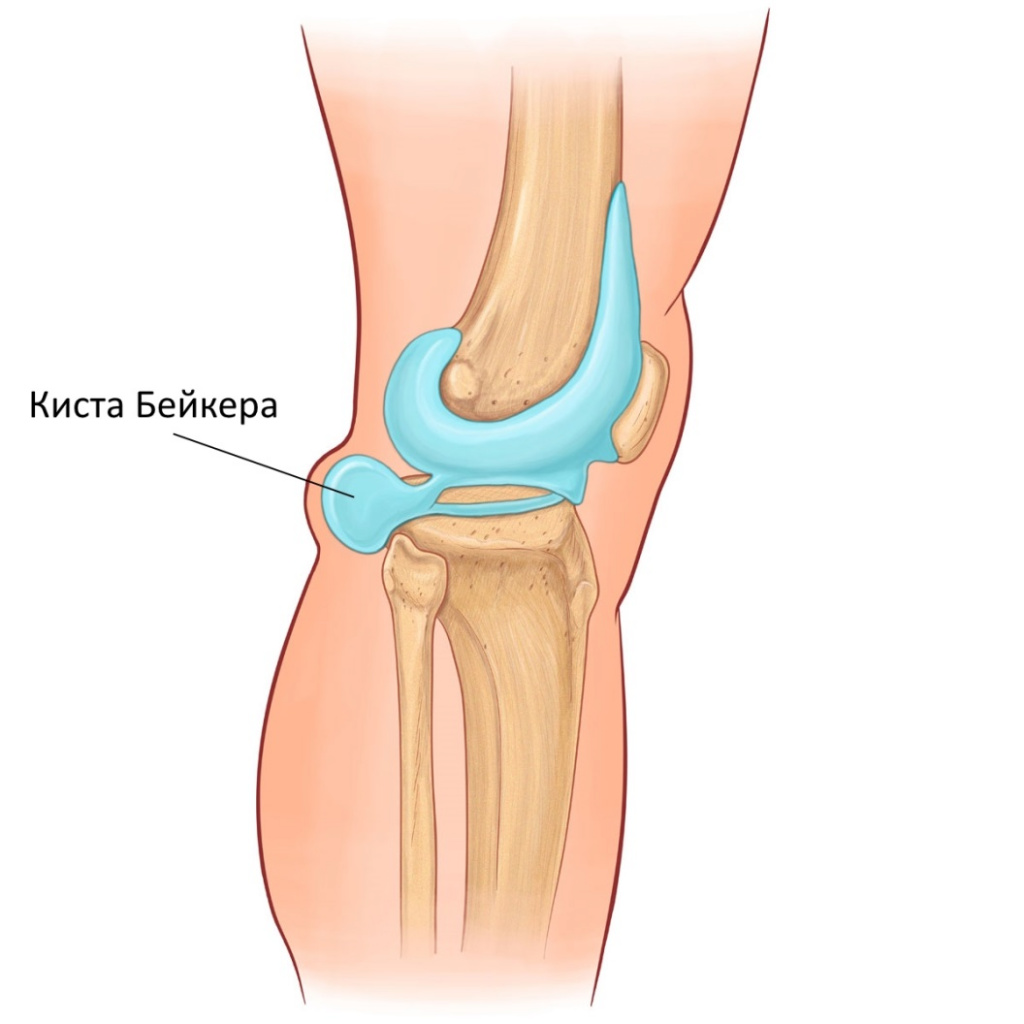

Анатомия коленного сустава: изучение анзерита и его влияния